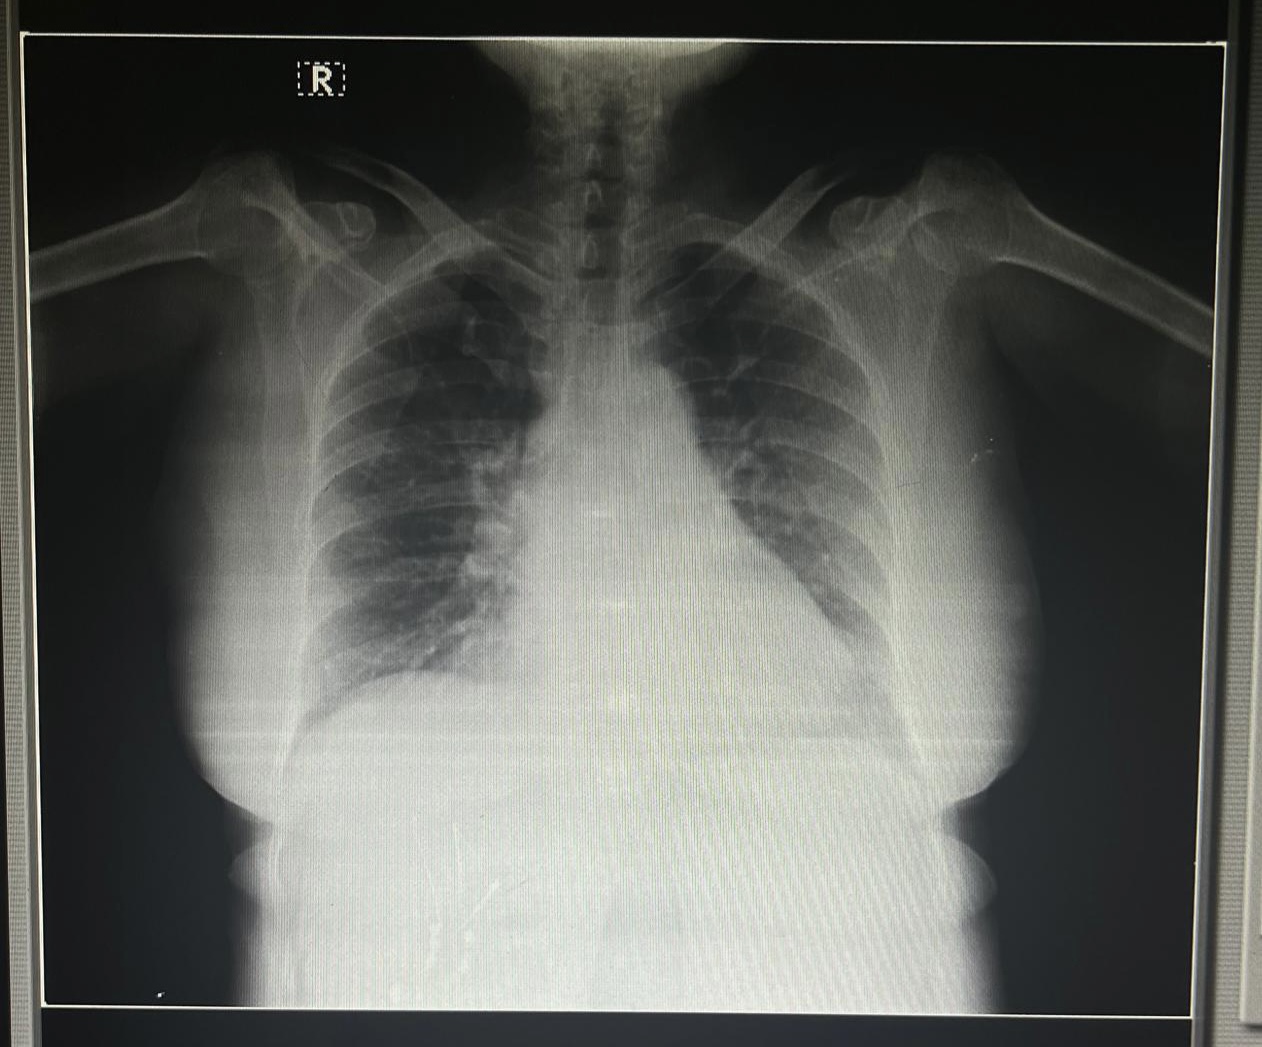

Rs-BAE+

Cvs-s1,s2+

2D echo

Tribal AR+ , no MR/TR

No Rwma , no AS/MS